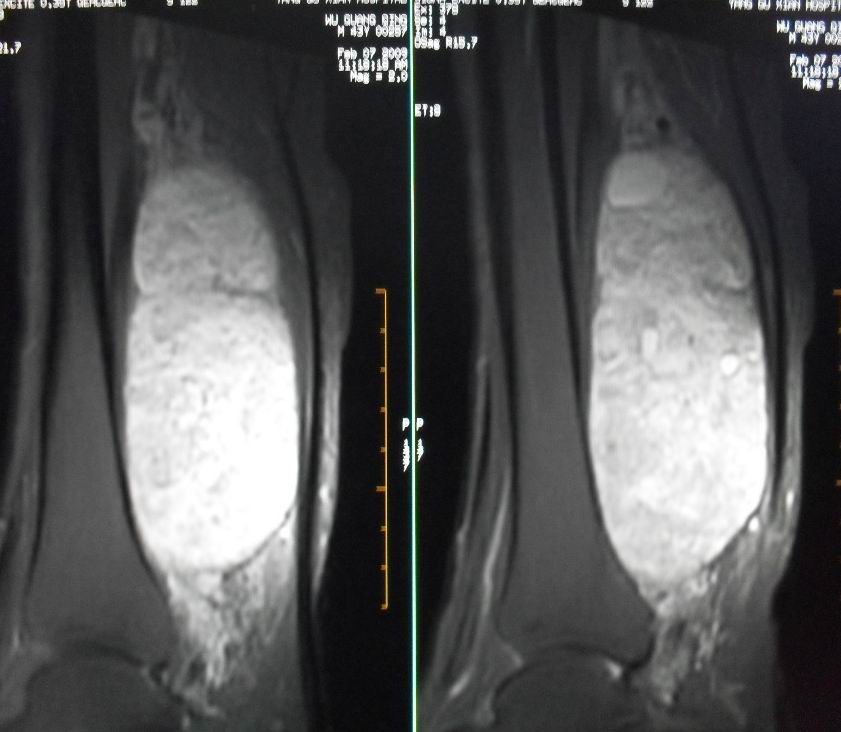

患者男43,右小腿后部软组织肿块2~3年,近期增大明显。平扫加强化。已手术。

1)呈等长t1混杂t2信号,其内见多发类圆形长t1长t2异常信号,病灶主要沿肌间隙生长,但有完整的包膜.gd_dtpa显示:病灶呈明显不均匀的强化,但未见迂曲的强化血管影.

呈等长t1混杂t2信号,其内见多发类圆形长t1长t2异常信号,病灶主要沿肌间隙生长,但有完整的包膜

本病例软组织肿块大,内信号不均匀,有多个囊变区,包膜完整,本片经山东省医学影像研究所mri室王主任会诊术前考虑良性肿瘤,不排除恶变,在北京某医院手术,穿刺及术后病理均为良性,未发现恶变。

本病例软组织肿块大,内信号不均匀,有多个囊变区,包膜完整,本片经山东省医学影像研究所mri室王主任会诊术前考虑良性肿瘤,不排除恶变,在北京某医院手术,穿刺及术后病理均为良性神经鞘瘤,未发现恶变。[face=宋体][/face]

谢谢楼主反馈手术结果!该病灶巨大,但与周围组织分界清晰,其内低密度规整,均支持良性病变。